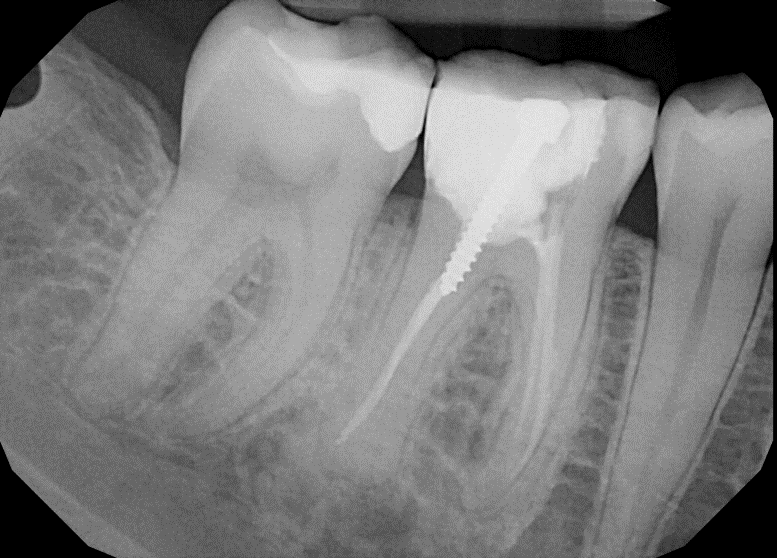

During a root canal, the pulp is removed and refilled with temporary cement. The rest of the tooth is then prepared for a crown or restored with filling material. For crown procedures, a device called a post is inserted to essentially strengthen and reinforce the tooth.

In the x-ray above, a post has been placed in the middle tooth and the tooth built up so that it is ready to be prepped for a crown.